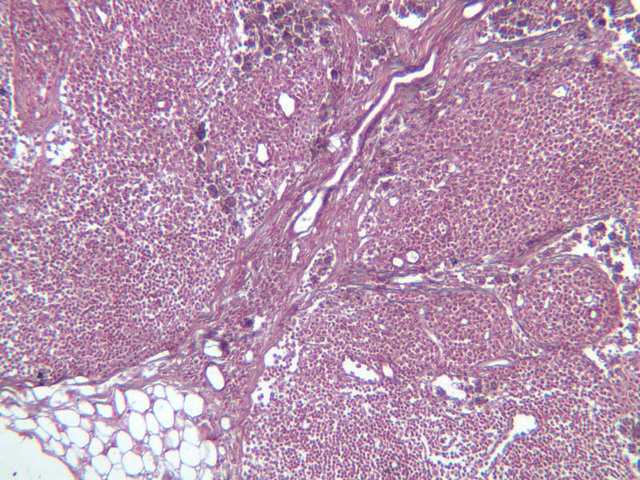

Lymph Nodes

When foreign substances or antigens get into body tissues, such materials are usually taken into the lymph and transported to aggregations of lymphoid tissue called lymph nodes (slide A-32, H&E [2.5x-labeled, 10x, 20x, 40x] [2.5x-labeled, 10x, 20x] [2.5x, 10x, 20x-labeled, 40x]; A-33, H&E [2.5x, 10x, 20x, 40x]; A-34, retic [2.5x, 10x, 20x, 40x-labeled]; A-35, H&E [2.5x, 10x, 20x, 40x]), which are composed of lymph nodules invested by a distinct connective tissue capsule. The node is visibly separable into a cortex, where the densely stained nodules are concentrated, and a light staining medulla (A-32 [2.5x, 10x-labeled, 20x, 40x]). Strands, or trabeculae, of connective tissue separate the node into cortical compartments and join centrally in the node to emerge at the indented side known as the hilus. Small arteries and veins enter and leave the node at the hilus, being distributed in the node through the trabeculae. Capillary branches from the arteries are spread throughout the lymphoid node. Multiple afferent lymphatic vessels penetrate the capsule of the node, emptying into a subcapsular sinus which is a relatively cell-free zone (A-32 [2.5x, 10x, 20x, 40x-labeled]). Unidirectional flow of lymph from the afferent lymphatics into the sinus is assured by the valves in the vessels. From the subcapsular sinuses, lymph percolates through the relatively unobstructed cortical sinuses to the medulla. During this flow the lymph is filtered by phagocytes and foreign antigens are presented to lymphocytes by dendritic cells, the resident antigenpresenting cells. Nodules are formed as needed and subsequently disappear. Lymph finally reaches the medullary sinuses bounded by wide cords of tissue and passes out of the node at the hilus through the sole efferent lymphatic vessel.

The lymphoid tissue of a node is thus divisible into the nodules in the cortex and looser cords in the medulla. In the cortex, carefully examine a secondary nodule, composed of a dense outer rim of cells and a more loosely organized core (germinal center). In between the nodules find larger cells with pale, oval nuclei. These are reticular cells and will be most easily identified in the reticular-stained preparation (A-34 [2.5x, 10x, 20x, 40x] [10x, 20x, 40x]). The reticular fibers cells make up the CT scaffolding of the lymph node. Note that there are fewer reticular fibers in the germinal centers. Medium-sized cells with pale nuclei, particularly cells with a prominent nucleolus, may be progenitor cells of new lymphocytes. Macrophages present in the nodule are hard to distinguish unless they contain phagocytosed material. In the medulla, cell types in the cords are easier to distinguish because cytoplasmic size and extent can be seen. For example, the differences between large lymphocytes and reticular cells can be seen. Several types of granular leukocytes are frequently found in the cords in addition to the expected population of lymphocytes and plasma cells.